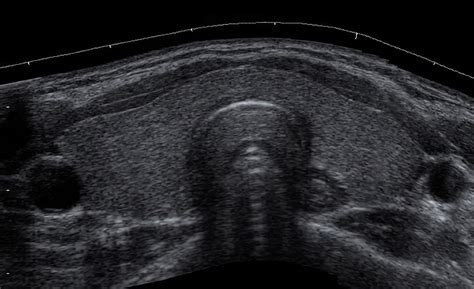

La procedura dell'agoaspirato tiroideo è relativamente semplice e rapida. Utilizzando un ago molto sottile (generalmente di calibro 23-27 gauge), inserito nella parte anteriore del collo, si raggiunge il nodulo sospetto. L'ago viene guidato sotto la supervisione dell'ecografia, che permette di visualizzare con precisione l'area attraversata dall'ago e il nodulo stesso. Questo approccio ecoguidato migliora significativamente l'efficacia dell'esame, minimizzando al contempo il rischio di danneggiare strutture circostanti come vene, arterie e nervi. In passato, questa procedura veniva eseguita a mano libera, basandosi sulla palpazione, ma l'ecografia ha reso l'esame molto più sicuro e accurato, permettendo anche di analizzare noduli non palpabili.